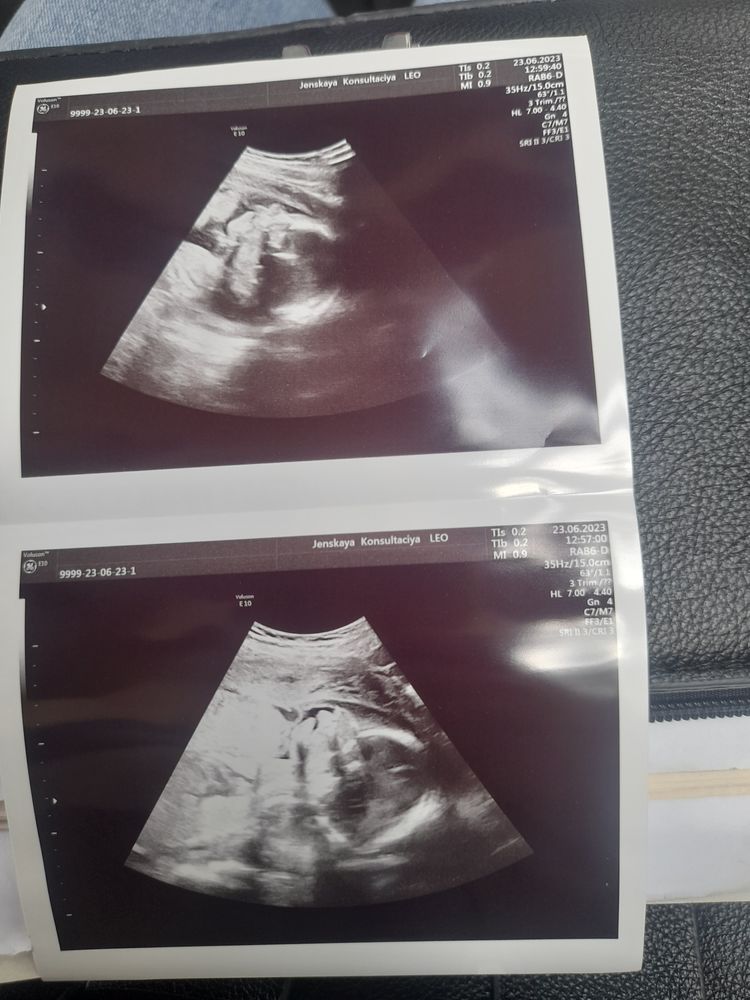

Странное узи беременности

Не вижу ничего плохого в узи. Это ж Вам не фото. Носик, рот, голова, ручка... Всё видно 🤷‍♀️ а всякие смазывающие моменты всегда присутствуют. И пуповина может в кадр попасть, и воды дают искажение. Вот мы женщины странные. Врач говорит, что всё нормально, а вот нет... Нам надо найти повод, чтоб попереживать, мол как то подозрительно, что всё нормально 😂

Узи это наука света и тени. Родится вообще другое поверьте 😅

Сходите на 3D УЗИ) А так да, фото на УЗИ может быть совсем не обычным) сканирование же идёт по плоскостям и даёт искажения, даже при малейшем движении)

Я на своем узи тоже заячью губу усмотрела. Долго ржал специалист узи...